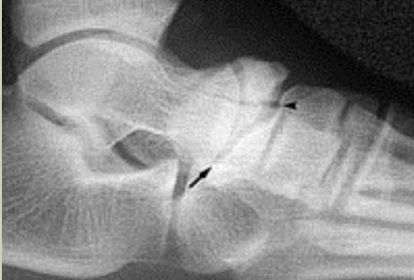

| What is this? What is shown by A and B? | STJ coalition A = talar neck spurring B = Halo or 'C' sign |